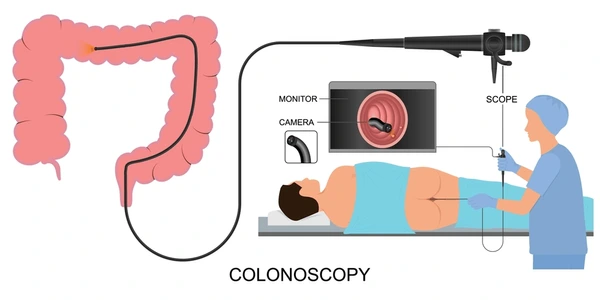

تعرف على خدمات منظار القولون في الكويت عبر موقع الدكتور فهد الابراهيم أفضل دكتور جهاز هضمي بخبرة عالية وتقنيات حديثة.

اكتشف تفاصيل سعر منظار القولون الكويت من خلال موقع الدكتور فهد الابراهيم أفضل دكتور جهاز هضمي في الكويت.